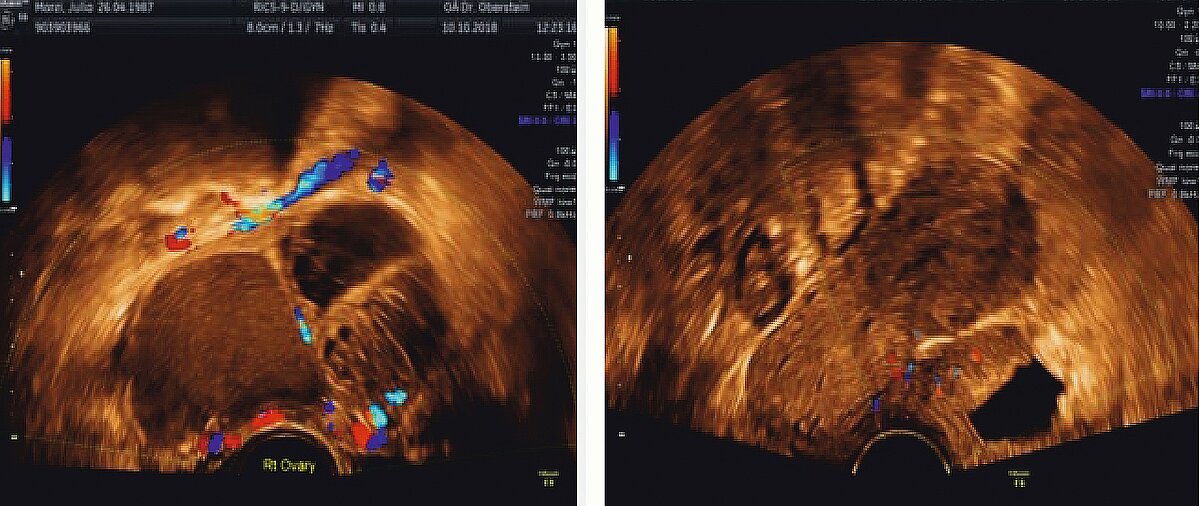

Die heute wohl wichtigste diagnostische Methode neben der akribischen Anamneseerhebung und der sachgerechten gynäkologischen Untersuchung ist die Transvaginalsonographie (TVS). Durch die systematische Befunddarstellung, wie in den IDEA- und MUSA-Konsensuspapieren [31, 32] aufgeführt, sollte es bei etwas Training in Klinik und Praxis möglich sein, insbesondere bei tief-infiltrierender Endometriose, eine zutreffende Diagnose zu stellen. Hierzu kann man heute sogar die Darstellung der sacralen Nervenwurzeln zählen. Beispiele für das ovarielle Endometriom sowie die Blasenendometriose sind in (Abb. 4) gegeben.